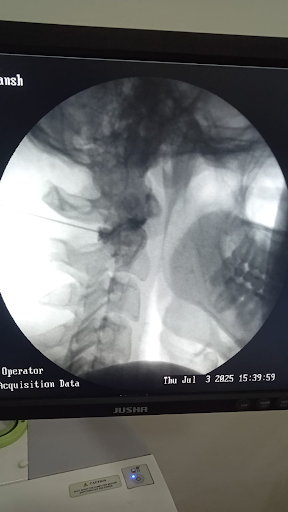

Patient undergoing cervical medial branch block under fluoroscopy at Alleviate pain Clinic , Bengaluru. Image Courtesy- Alleviate

- Cervical medial branch block – pain relief and diagnostic tool.